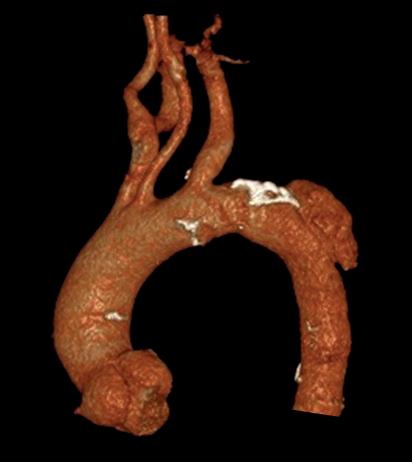

Left: Pre- and postoperative images (courtesy of Dittmar Böckler) of the first European implantation of the Gore Tag TBE; above: Dittmar Böckler performing the implantation